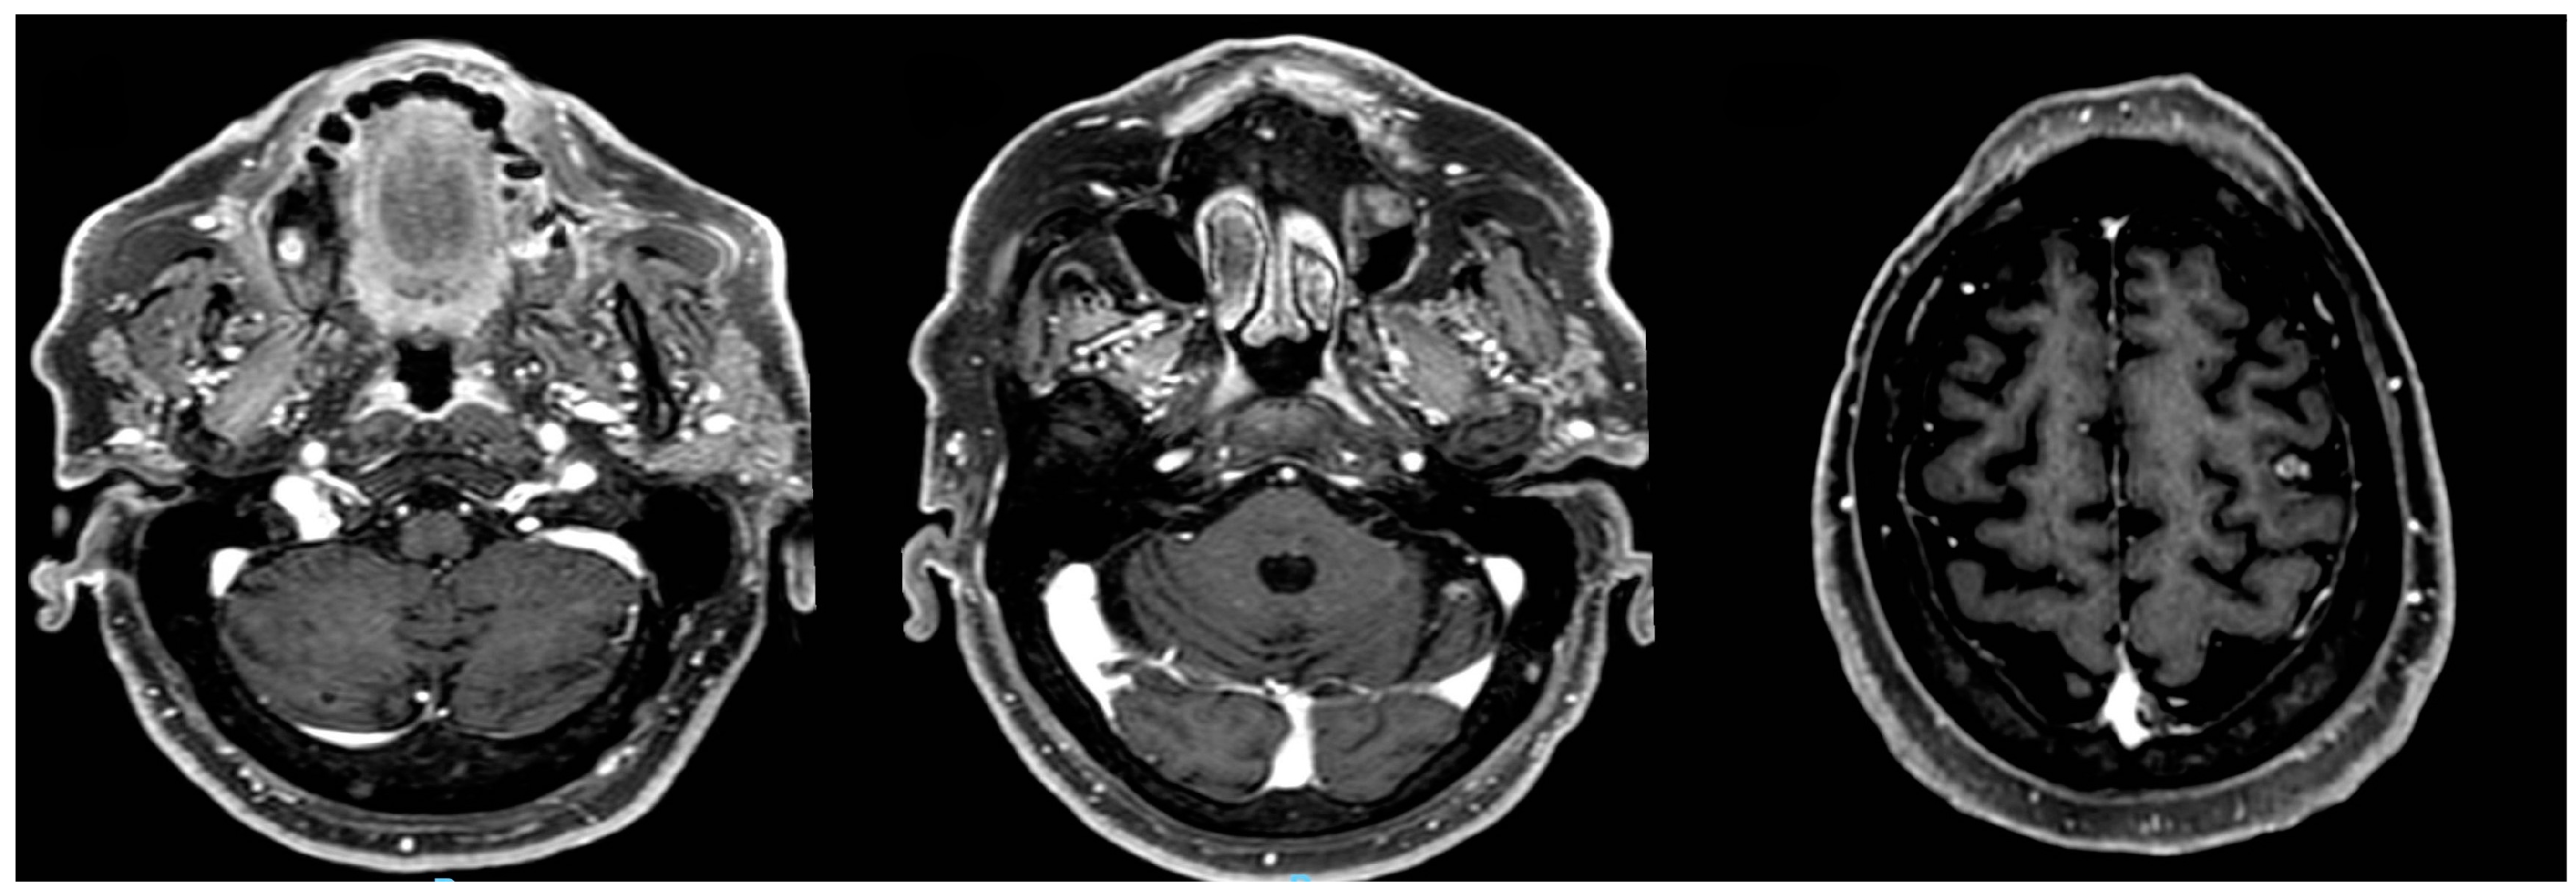

After one week, a total body computed tomography scan (TB CT scan) was performed, revealing a solid nodular, expansive mass (39 mm) in the right upper lobe of the lung and multiple lymphadenopathies in the mediastinum (paratracheal and subcarinal) (Figure 2a).

Fluorodeoxyglucose positron emission tomography (FDG PET) (Figure 2b) confirmed the presence of multiple hyper-capturing lesions consistent with the CT scan findings: right superior lobe (SUV 16.8), mediastinal nodes, plus lesion on the occipital bone. A cT2N2M1c stage IV lung cancer was diagnosed with CEA and Ca19.9 of 15.4 ng/mL (<6) and 65.6 UI/mL (<37), respectively.

Figure 2. Lung tumor imaging at diagnosis. Legend: (a) lung tumor in the right upper lobe on CT scan; (b) PET-FDG hyper capturing lesion on right superior lobe and mediastinal nodes.